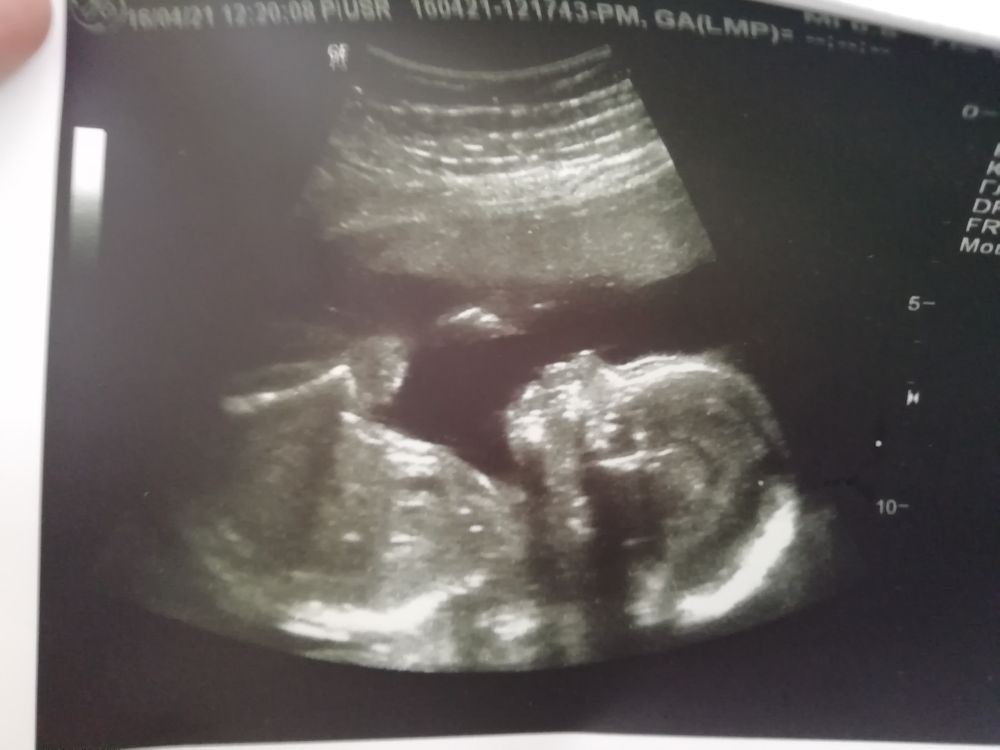

Второй скрининг❤️ фото

Ровно в 21 неделю съездили мы на скрининг. Все параметры в норме, вес почти 400г, пол подтвердили, у нас девчушка❤️